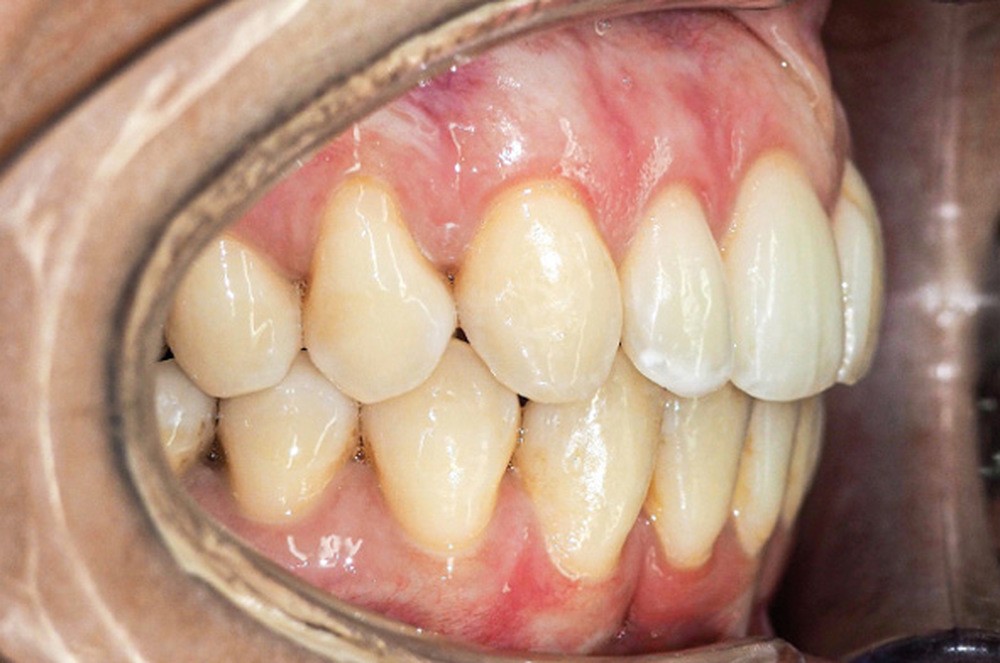

Examen endo-buccal (fig. 2a-e)

L’arcade maxillaire est parabolique, la 12 présente une légère mésio-rotation. L’arcade mandibulaire est également parabolique avec un encombrement antérieur estimé à 6 mm. On note une dyschromie de la 31, dont le test de vitalité est négatif. Le parodonte est fin.

En occlusion, on note une relation de Classe I molaire bilatérale avec un surplomb normal et une supraclusion. Les médianes incisives sont concordantes.

Les incisives maxillaires sont de forme triangulaire [1] et l’indice de Bolton est de 97 % qui traduit la présence d’une DDD par excès mandibulaire.